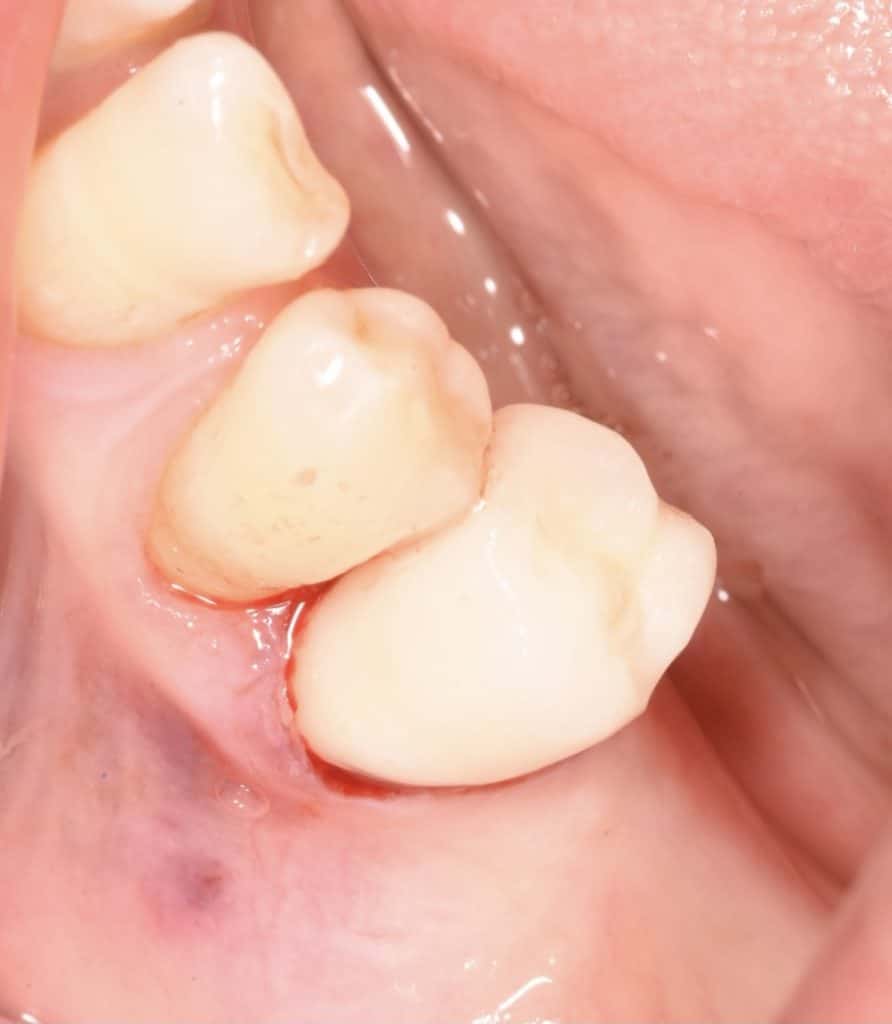

⛔️use fiber post to build up the core.

⛔️prepAration & digital scanning.

⛔️ zirconia crown cementation done with dual cure resin cement.